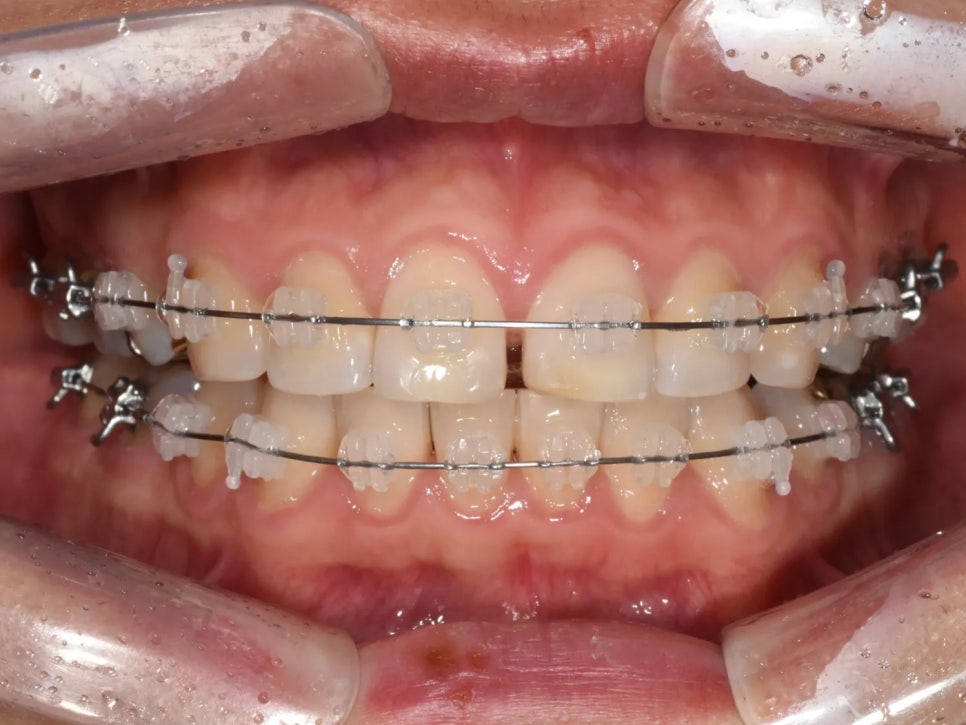

치료 과정 ② - 미니스크류를 이용한 전체 치열 후방이동

치아 배열과 과개교합 개선이 완료된 후, 드디어 본격적인 후방이동을 시작했습니다.

여기서 핵심 장치가 바로 미니스크류(TAD, Temporary Anchorage Device)입니다. 미니스크류는 뼈에 직접 심는 아주 작은 나사로, 치아를 당길 때 절대적인 고정점 역할을 합니다.

사랑니를 뺀 자리의 공간을 활용하여, 미니스크류에 연결된 탄성 체인으로 치열 전체를 조금씩 뒤로 이동시켰습니다.

미니스크류 식립 후 전체 치열 후방이동을 시작한 모습